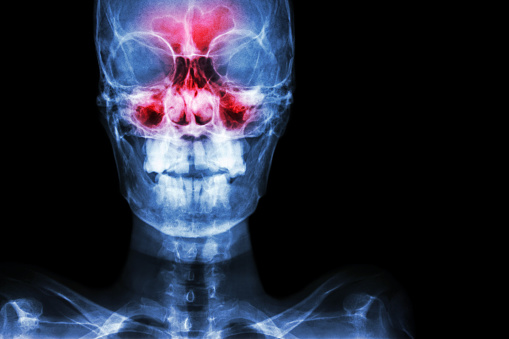

- التهابات الجيوب الأنفية: الجيوب الأنفية عبارة عن العديد من التجاويف والتي تقع داخل فجوة الجمجمة، وتؤدي العدوى إلى انتفاخ الأغشية المخاطية الموجودة وانسدادها، ويتضمن التهاب الأنف وانسدادها علاج المسبب نفسه: